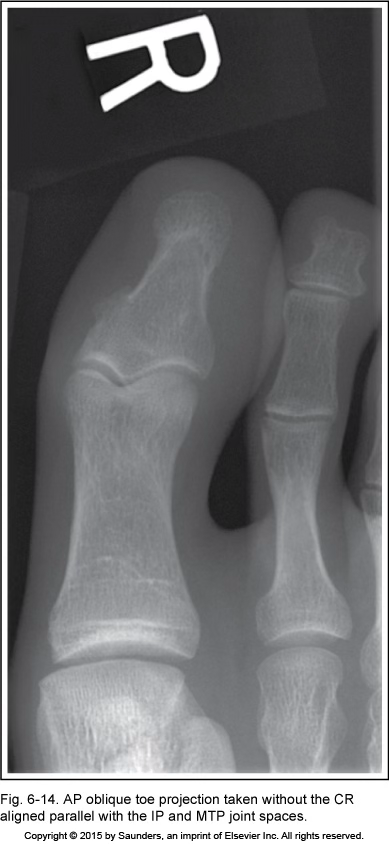

AP oblique toe

CR not aligned parallel with the IP and MTP jt spaces